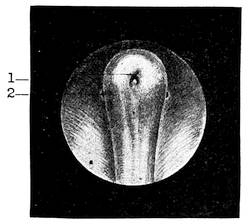

In the male the genital tubercle increases enormously in size to form the penis. Its extremity becomes bulbously enlarged and forms the glans penis. The lips of the groove or rather of the vestibule, since by this time the urogenital membrane had broken through and had transformed the sinus urogenitalis into the vestibule, the so-called genital folds, meet together and fuse, thus converting the vestibule and the groove into the terminal portion of the male urethra and bringing it about, that the ductus ejaculatorii and the sinus pocularis open upon the floor of that passage. The prostate, consisting of several independent glands, has also its openings at this point. In its development the prostate belongs to the urethra as well as to the sinus urogenitalis. The two genital swellings are brought closer together in the male and form the scrotum, a sac containing two separate pouches into which the testes descend.

Urethra.—The urethra is divided into three parts, the pros34tatic, the membranous and the cavernous parts. The prostatic part is the widest portion of the entire urethra. It is surrounded by an unstriped muscular layer and the muscles of the prostate. The membranous part is the narrowest, shortest, and most thin-walled portion of the three parts of the urethra. It is entirely surrounded by the muscular fibres of the diaphragma urogenitale, which takes here a circulatory course. It is in this way situated35 on the border-line of the abdominal cavity and the exterior, within the abdominal wall. The cavernous portion of the urethra is surrounded by the corpus cavernosum urethrae. This portion shows two dilatations, one in the bulbous part, just anterior to the termination of the membranous part, where the ducts of the two Cowper’s glands open; the other dilatation is near the end, behind the meatus, forming the so-called fossa navicularis. The meatus itself is the narrowest part of the entire urethra. Numerous mucous crypts, the glands of Littré and certain lacunae, the largest among them near the fossa, open into the lumen of this part of the urethra. The entire urethra is lined with a cylindrical epithelium, except at the fossa navicularis. The latter is covered by a layer of pavement epithelia. The length of the urethra is about 18 centimeters. In the usual state the urethra possesses only a virtual lumen, i. e., the walls touch each other.